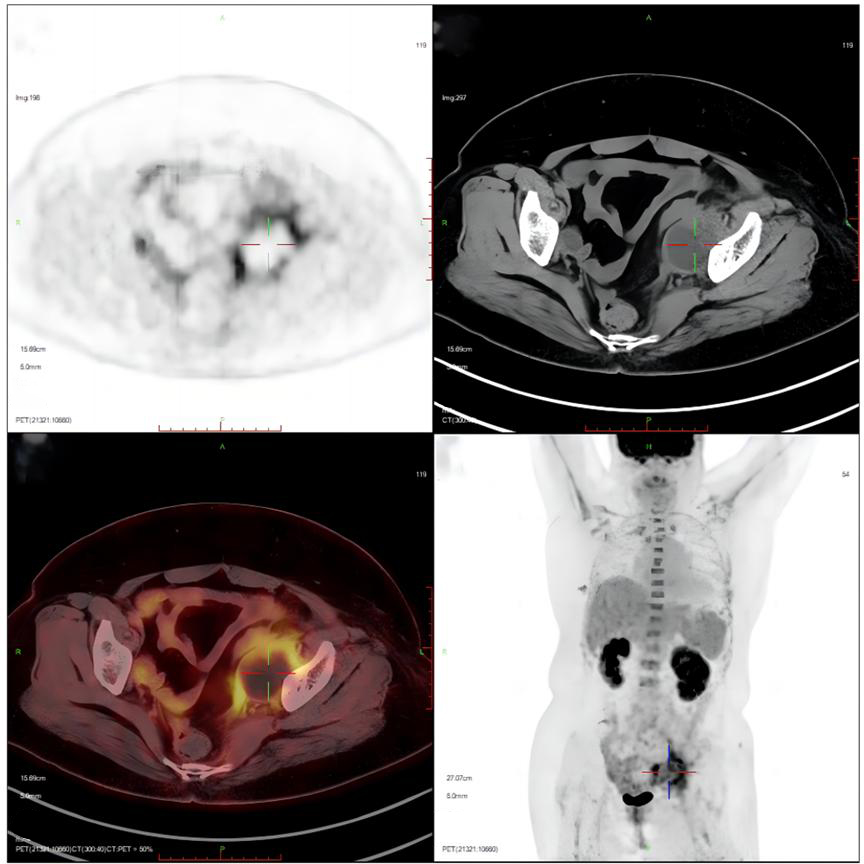

Ancillary investigations: Ultrasound + Doppler (lower extremity arteries): both lower extremity arteries were patent. Colour pelvic ultrasound: anechoic left iliac fossa, about 4.7 cm × 4.3 cm, with punctate echoes and poor translucency. PET-CT: left pelvic cystic foci, lymphocysts with infection (Figure 1). Blood count: haemoglobin 78 g/L. Blood culture: negative.

Figure 1. The result of positron emission tomography (PET-CT). Suggestive of left pelvic cystic foci surrounded by patches of irregular soft tissue with increased glucose metabolism, consider lymphocysts with infection.